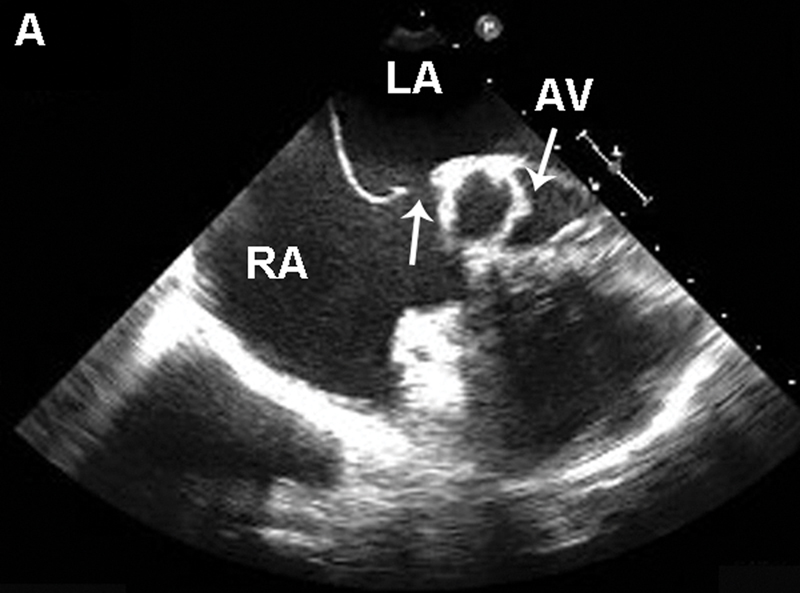

فحوصات تشخيصية لبعض امراض القلب والشرايين التاجية